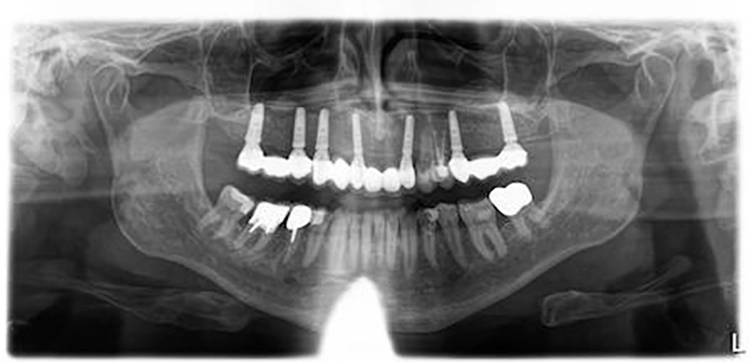

Der Patient ist Nichtraucher mit gutem Allgemeinzustand und nach Anamnese ohne kritische oder für einen eventuell notwendigen Knochenaufbau risikobehaftete Komorbiditäten [3]. Seine Teleskopprothese im Oberkiefer war nur noch über die drei Pfeilerzähne 13, 22 und 23 verankert.

Der Therapieplan wurde in Abstimmung mit dem Patienten erstellt. Dabei war zu berücksichtigen, dass der Patient über den gesamten Behandlungszeitraum bis zur Fertigstellung der definitiven Restauration unbedingt kaufunktionell versorgt zu bleiben wünschte, da er zwischenzeitlich in Campingurlaub gehen wollte. Aufgrund der starken Pneumatisation der Kieferhöhlen wurden im posterioren Bereich beidseitig ein externer Sinuslift und nach Ausheilung der Strukturen die Implantation von sieben Implantaten (Conelog, Camlog, Wimsheim) mit unterschiedlichem Durchmesser und je 13 mm Länge geplant.

Die Implantatmaße und -positionen sowie der Umfang der Sinusbodenelevation wurden dabei in Sinne eines „backward planning“ anhand von DVT-Aufnahmen bestimmt. Zahn 13 sollte noch vorübergehend erhalten bleiben, um zusammen mit den bleibenden Zähnen 23 und dem entsprechend kariesbehandelten Zahn 24 bis zur Fertigstellung der definitiven Restauration der alten Teleskopprothese als Interimsersatz Halt zu geben. Als definitive Versorgung wurden drei VMK-Brücken auf NEM-Gerüsten vorgesehen. Damit sollte auch die natürliche Bezahnung im Unterkiefer von 37 bis 47 abgestützt werden.